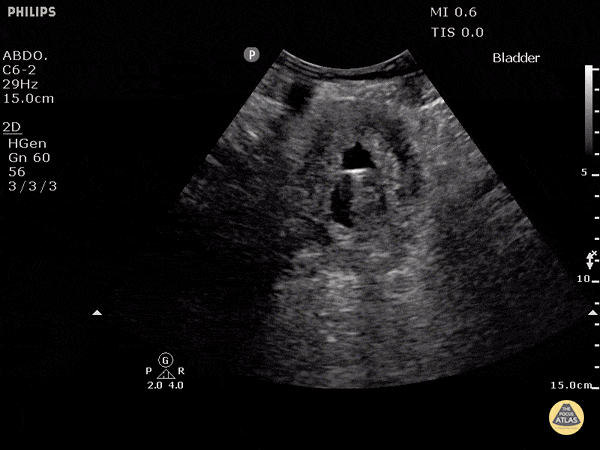

Renal/GU - Bladder Contracted with Indwelling Catheter

An echogenic foley catheter with the balloon inflated can be seen floating inside the anechoic urine within the bladder. Dr. Justin Bowra et al.